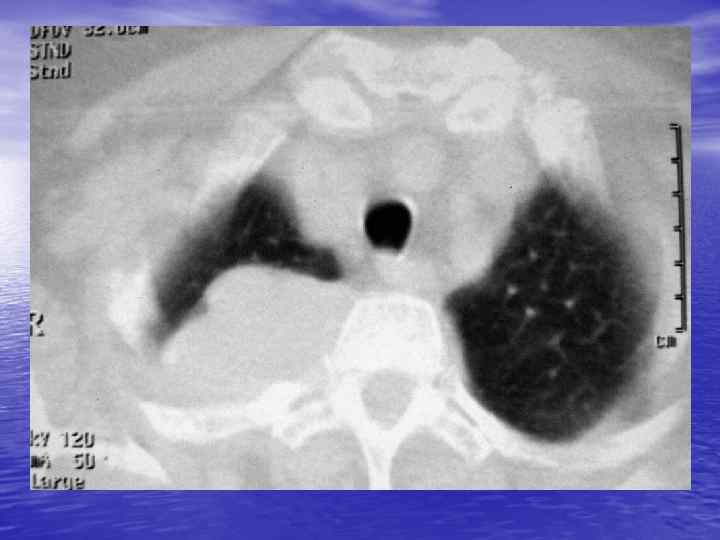

Денситометрический анализ Определение основных видов патологических образований: - обызвествленных - мягкотканных - жидкостных - жиросодержащих - воздухсодержащих

Преимущества спиральной КТ: ü Возможность проведения исследования с болюсным ü ü ü ü ü контрастированием Высокая разрешающая способность; Высокая скорость исследования; Получение высококачественных изображений костных структур; Возможность обследования всего тела; Возможность проведения исследования больных под наркозом; Возможность детальной оценки состояния крупных и периферических сосудов в условиях искусственного контрастирования; Высокая информативность метода при черепномозговых травмах в остром периоде; Ранняя диагностика ишемических и геморрагических инсультов; Метод выбора для диагностики заболеваний легких; Планирование лучевой терапии.